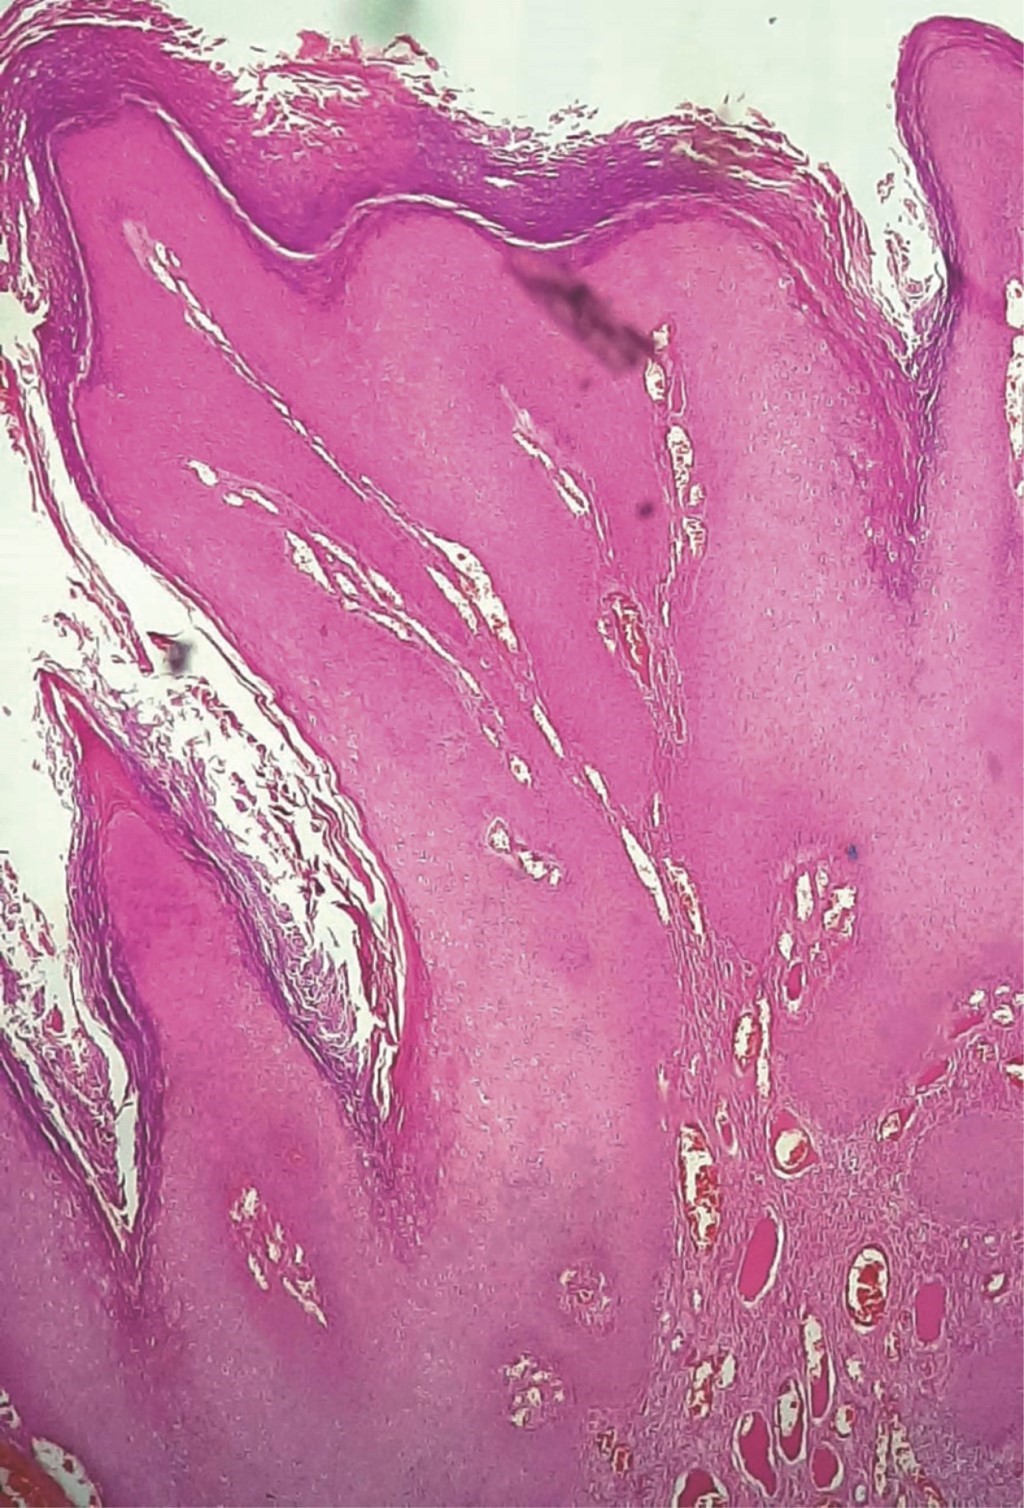

The specimens were sent for histopathologic study (Figure 3), identifying an exophytic growth pattern in microscopic sections with stratified flat epithelium with significant acanthosis-basal cells with mild hyperchromasia and atypia. The basal layer was intact (Figure 4). In the superficial thirds were cells with vesicular nuclei, clear vascular cytoplasm (koilocytes), and a few mitosis figures (Figure 5). The superficial layer demonstrated a slight increase in keratin lamellae. The fibrous stroma had multiple congestive vessels. According to these findings, the diagnosis of Buschke-Lowenstein disease with low-grade squamous intraepithelial anal lesion AIN 1 was established. The patient was referred to the outpatient clinic two months after the surgical procedure; the perianal region was adequately healed, with no evidence of new condylomatous lesions or fistulas (Figure 6).

Figure 4